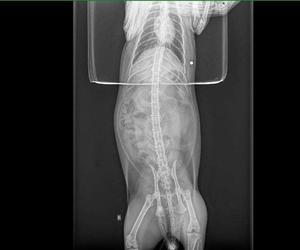

Właścicielka z kotem natychmiast pojechała do weterynarza. Smutną prawdę u weterynarza wykazało prześwietlenie RTG. Okazała się, że kotek został postrzelony śrutem z wiatrówki. Sadysta trafił w go w brzuszek.

Śrut utkwił w jamie brzusznej, ale na szczęście z boku. – Śrut mógł przecież uszkodzić jakiś organ i kot padłby. Nie rozumiem komu przeszkadzają koty – pisze nasza czytelniczka.

W styczniu 2021 r. doszło do podobnej sytuacji. Wtedy także ktoś postrzelił kota naszej czytelniczki. Cynamon został trafiony w okolice kręgosłupa. Na zdjęciu RTG było widać śrut przy kręgosłupie zwierzaka. Nikogo wtedy nie zatrzymano.